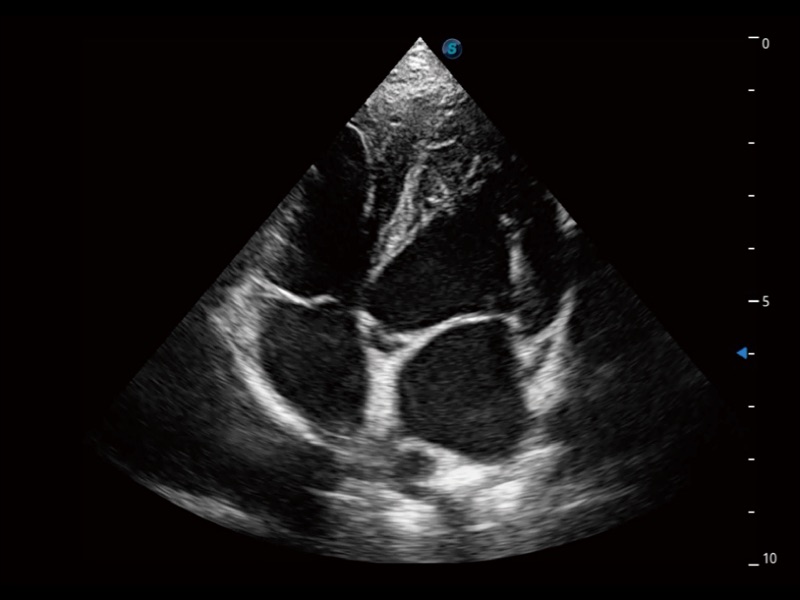

能够基于左心室壁追踪和辛普森法,自动计算射血分数,支持多个可移动点描迹,与手动测量相比,极大节省了动物医生的时间和精力。